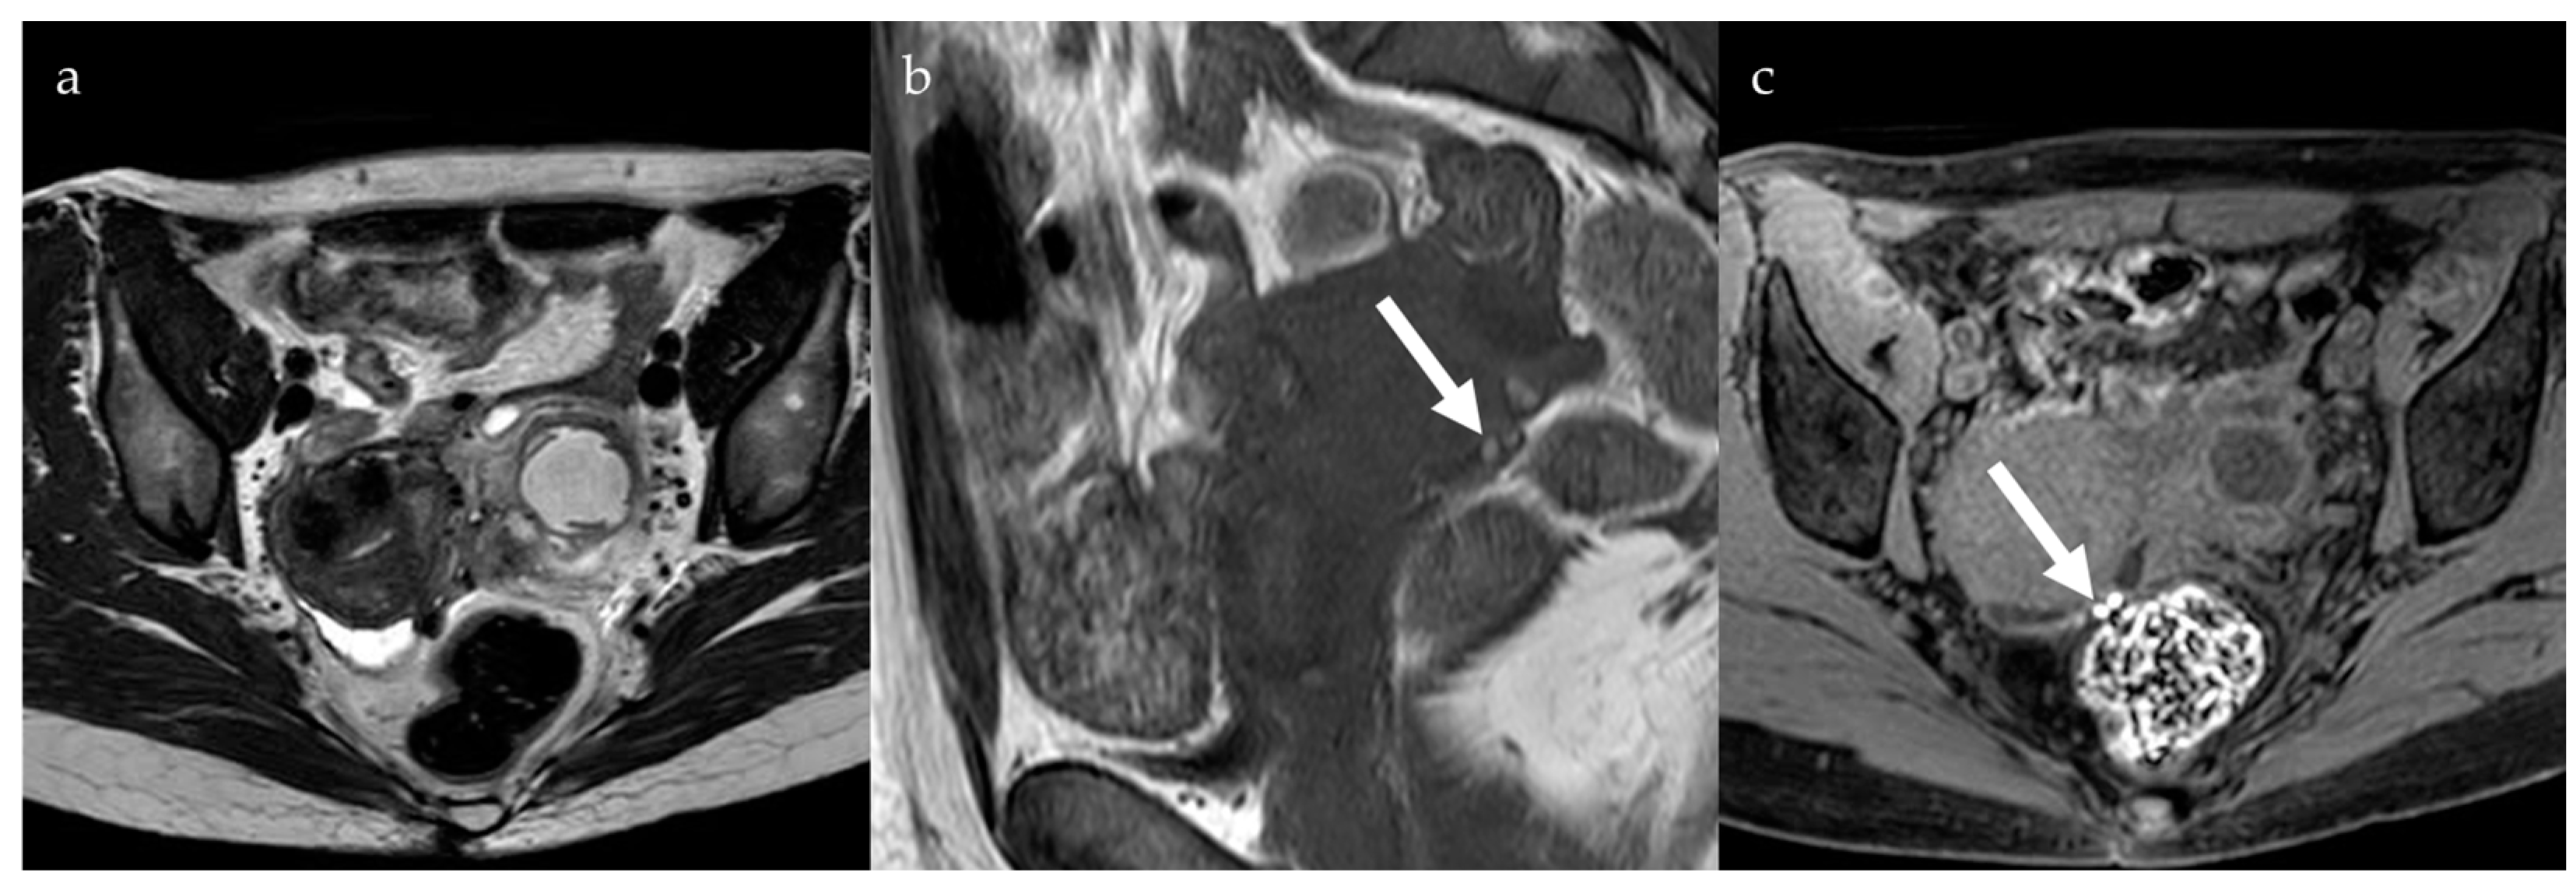

2.1. Endometrioma

2.2. Deep Pelvic Endometriosis